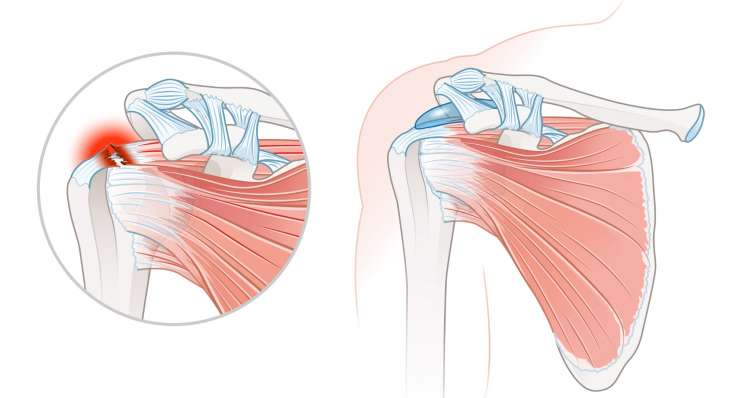

повреждение вращательной манжеты

Повреждение вращательной манжеты приводит к боли и потере функциональности плеча. В зависимости от результатов обследования, профессор, доктор медицины Франк Мартешлегер лечит это заболевание консервативным методом или с помощью артроскопии, проводя точную реконструкцию сухожилий.